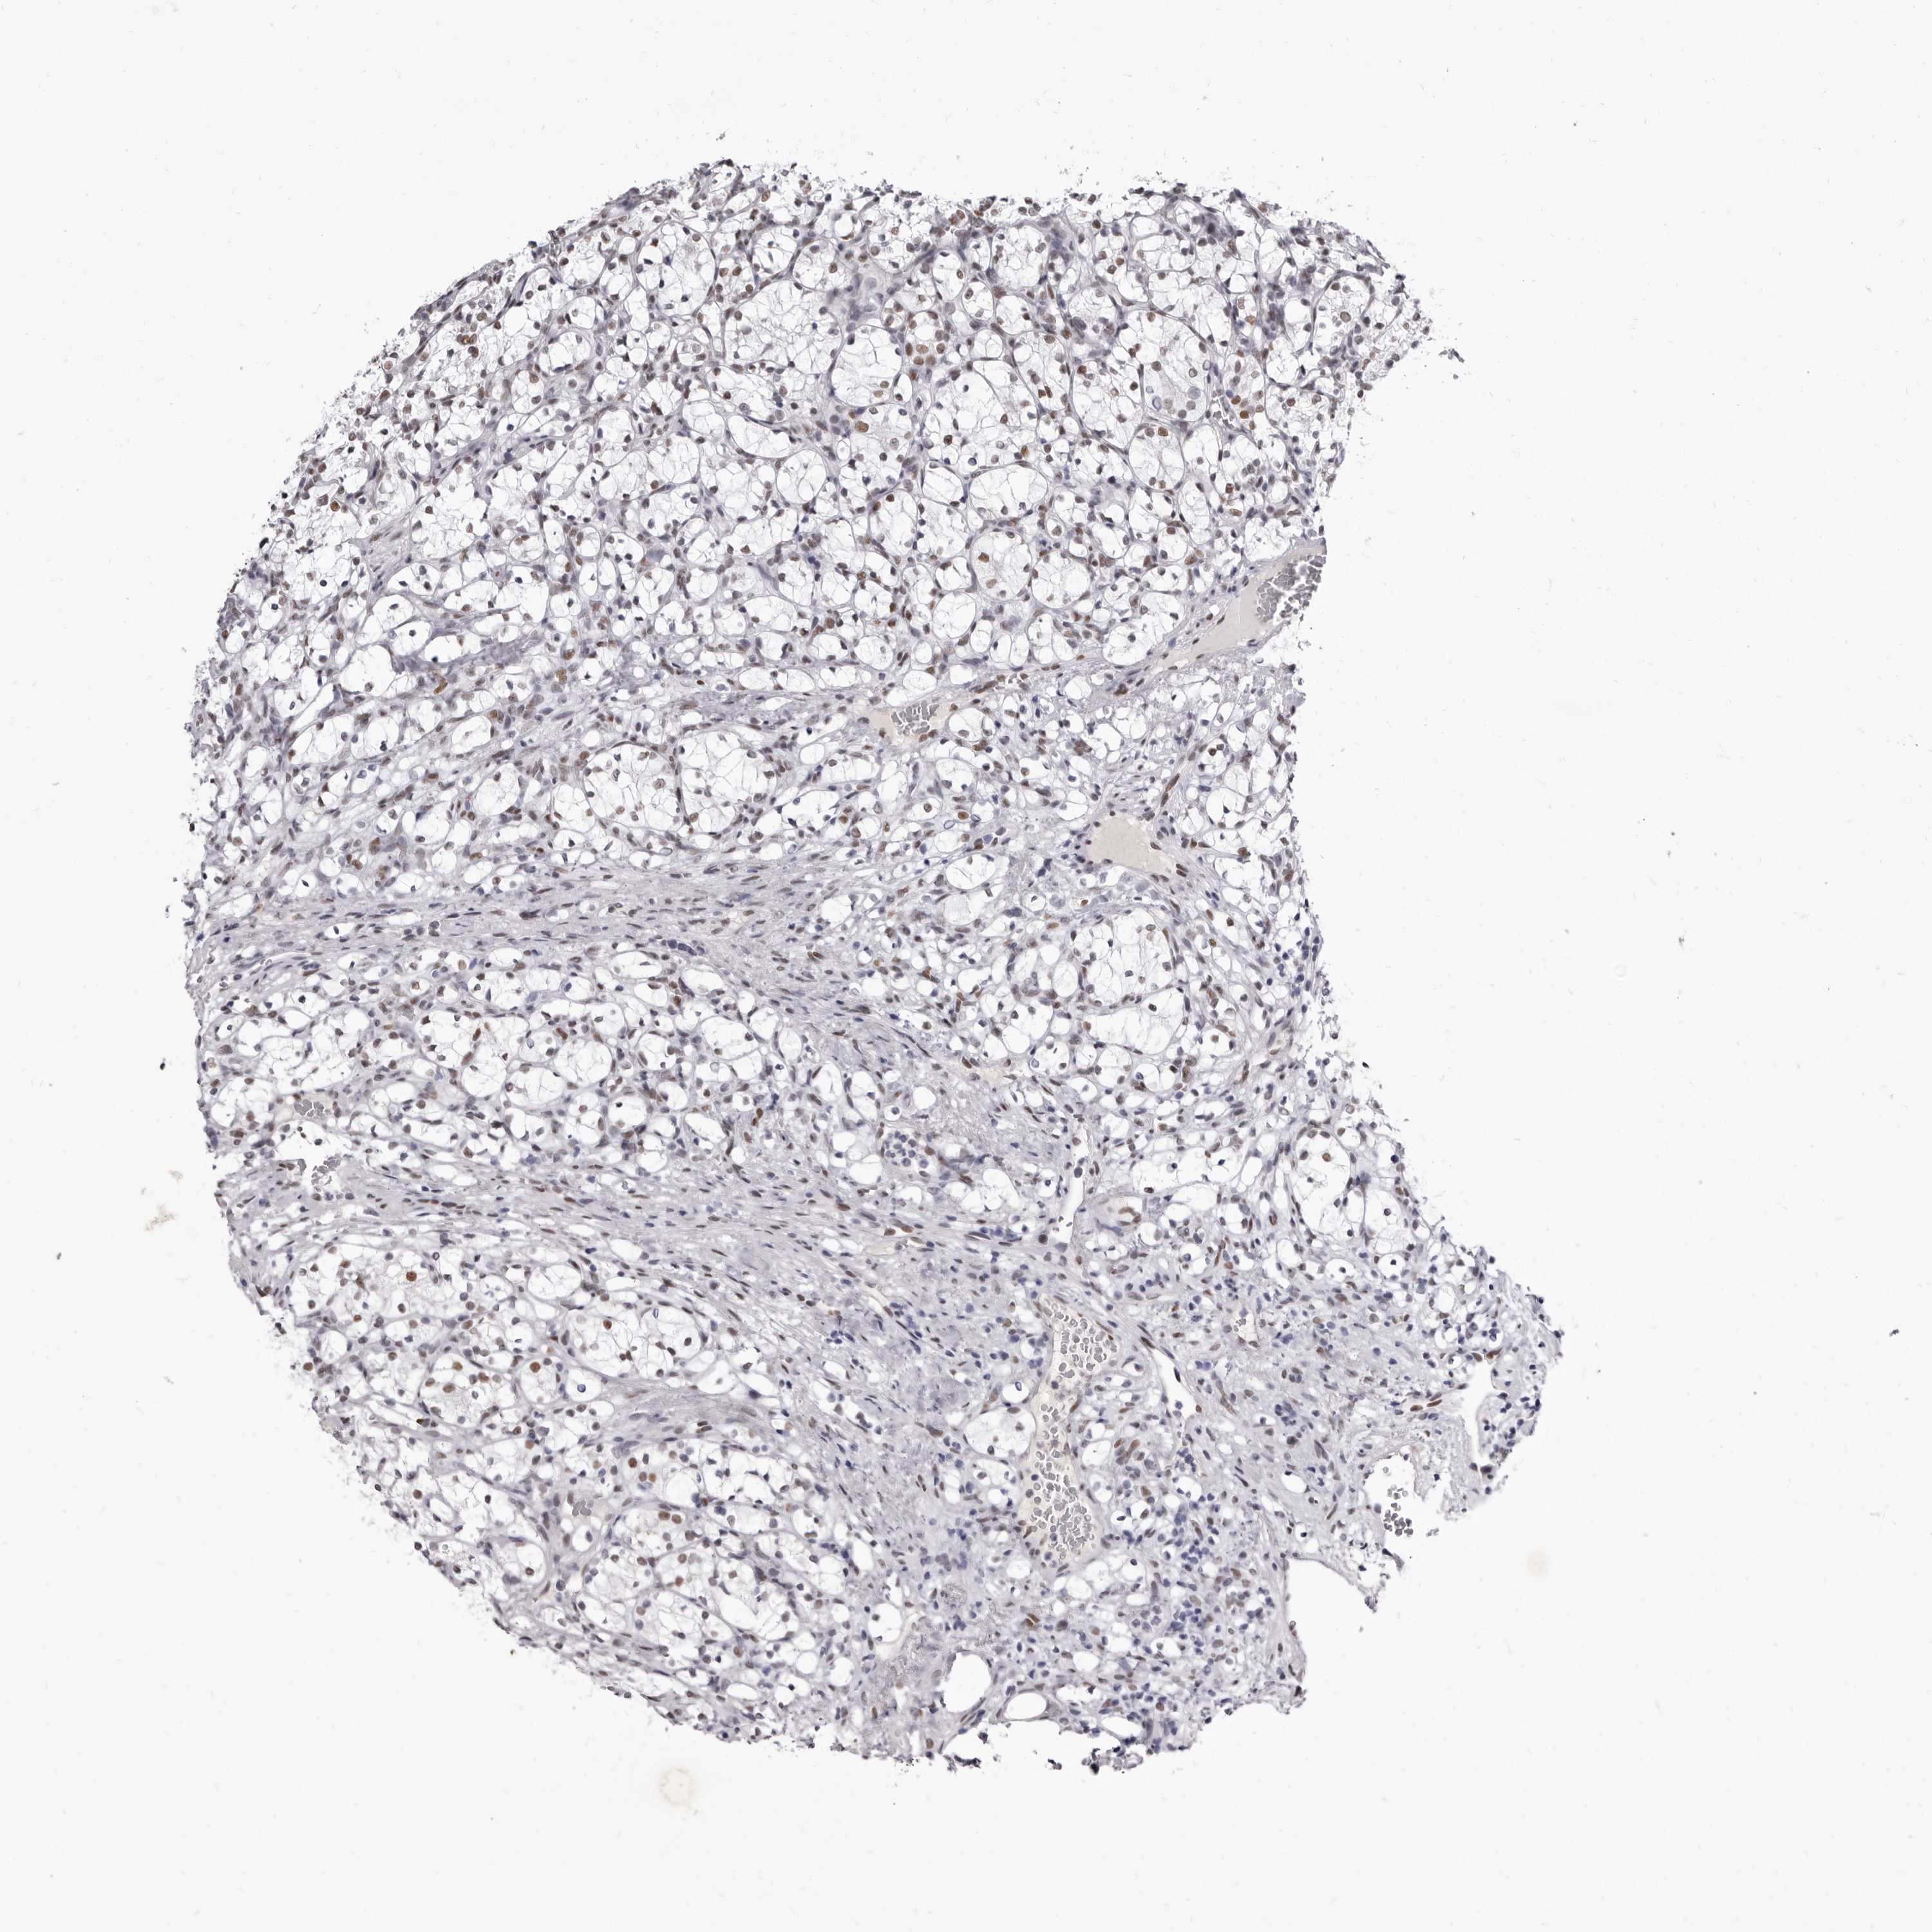

CANCER RENAL CANCER Show tissue menu

KICH TCGA KIRC TCGA KIRC VALIDATION KIRP TCGA PROTEIN RCC CPTAC PROTEIN EXPRESSION

KIDNEY RENAL CLEAR CELL CARCINOMA (VALIDATION) - Interactive survival scatter ploti

ZNF326 is potential prognostic, high expression is favorable in Kidney Renal Clear Cell Carcinoma (validation)

: 5.16

Average pTPM 5.7

Number of samples 100